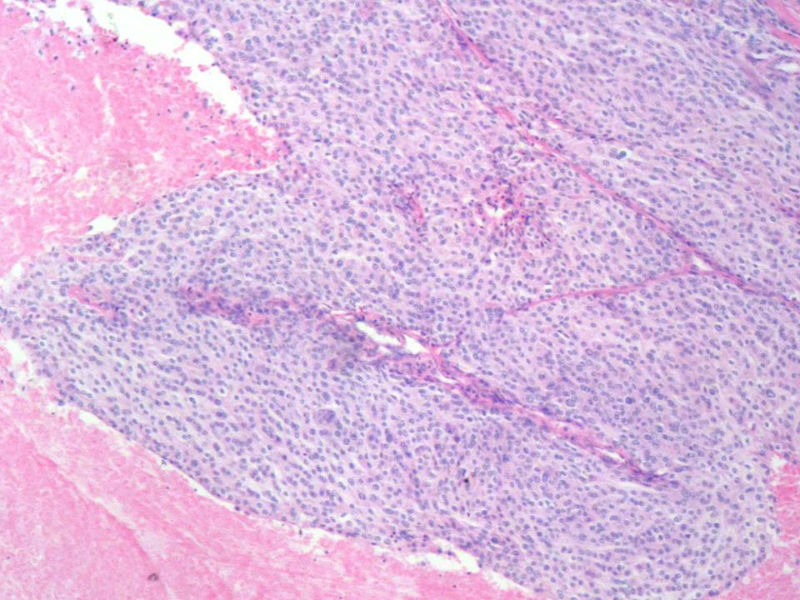

女,64岁,头晕半月,CT检查颅内左颞叶占位,侵犯颅骨和颞肌,手术切除肿物。肉眼,灰白色结节状肿物,3X3X2厘米,边界不清,切面灰黄色,质软。

特别提示:手术前曾做过介入肿瘤栓塞。镜下核分裂15/HP。脑左颞部占位图1

梭形细胞与上皮样漩涡状结构,富于细胞,见个别沙砾体,并见肿瘤性坏死。颅骨及其横纹肌等软组织内见肿瘤呈侵袭性生长。但细胞异型性不是很大。鉴别:

1)恶性脑膜瘤

2)非典型性脑膜瘤

由于非典型性脑膜瘤也可以发生地图状坏死,甚至侵袭性生长。需要计数核分裂数/10HPF,以资鉴别诊断。